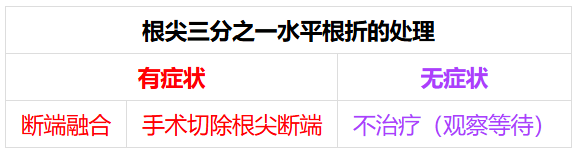

直接牙外伤(集中于牙齿小区域)是水平牙根折断的主要原因[1]。牙根水平折断概率极低,约1.2%-7%[2]。下颌前牙较少发生口腔外伤,其中下颌侧切牙根折报道最少,根尖三分之一根折更为罕见[2]。本例中,远中弯曲的长下颌侧切牙根尖三分之一根折及30毫米异常尖牙长度均属罕见。根中三分之一折断通常采用桩核修复进行冠方与根尖断端对位[2]。根尖三分之一根折大多无需治疗,采取观察策略即可[3]。根尖三分之一根折的处理取决于牙齿是否有症状[3-4]。有症状病例,非手术治疗仅需对冠方断端进行根管治疗;若持续性牙髓坏死导致患者就诊,则需手术切除根尖断端[3-4](图10)。根尖三分之一根折中,冠方断端移位可能导致两断端对位困难。有时过度松动的断端限制冠方与根尖断端对位,因此需非手术融合。本例牙齿轻度亚脱位,减少了断端融合的限制[4]。

图10. Jethi根尖三分之一根折处理分类(基于症状表现)